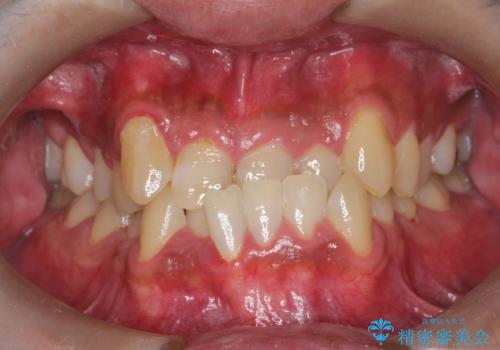

- 主訴:噛み合わせが反対になっているのを治したい

反対咬合と叢生改善のため、上下左右4番目の歯を抜歯し、審美装置にて矯正治療を行いました。